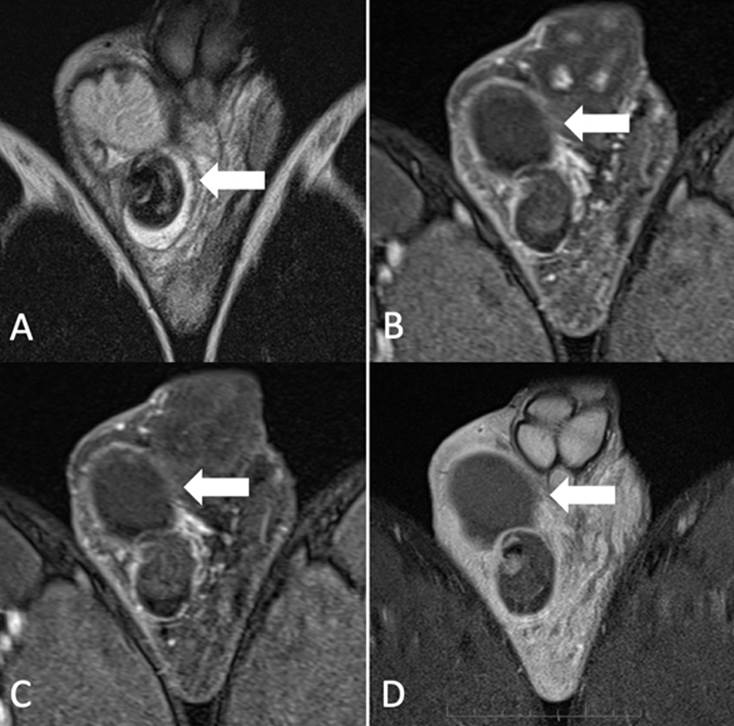

A) Imagen coronal secuencia T2. Signo de whirlpool (flecha). B, C, D) Imágenes coronales secuencia T1 registros dinámicos con contraste. Ausencia de captación de contraste en estructuras testiculares y funiculares derechas (flecha). Origen: Servicio de Diagnóstico por Imágenes. Hospital Italiano de Buenos Aires. Buenos Aires, Argentina. 2021.

Figura 2b Comparación de imágenes T2 y T1